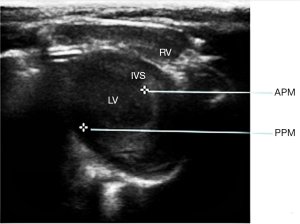

After the experimental animals were weighed, 2% sodium pentobarbital (40 mg/kg) was injected into the abdominal cavity. Under anesthesia, the left chest hair was cut using a cotton ball dipped in a depilatory agent, and after 2 or 3 minutes, the rats were washed with warm water, and the depilated part was dried with gauze. The rat limbs were fixed on the operating table in supine position, and the probes were placed on their left chest. After obtaining a satisfactory short-axis two-dimensional image of the left ventricle next to the sternum at the level of the papillary muscle, M-mode echocardiograms were obtained by placing the M-mode sampling line perpendicular to the septum and posterior wall of the left ventricle. The data were measured in 3–5 cardiac cycles to obtain the average value.

According to the above results, the weights of all groups increased significantly after 12 weeks (P<0.05), while heart rate had no significant change (P>0.05). Left ventricular ejection fraction (LVEF) and left ventricular fractional shortening fraction (LVFS) were not significantly decreased in the experimental group (Figure 6). LVEF and LVFS were increased in both the control group and sham group (P<0.05). Compared with the control group and sham group, LVEF and LVFS of the experimental group were decreased after 12 weeks (P<0.05).